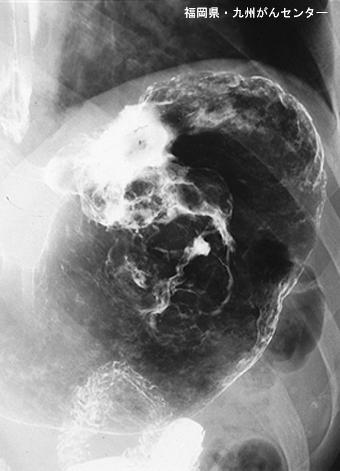

疾病(病理主体)的分类恶性上皮性肿瘤/腺癌

部位(按器官分)胃(部位)/体部

检查方法X线

肿瘤的肉眼分类5型(难以分类)/

肿瘤最大直径40以上

肿瘤的深度ss(a1)